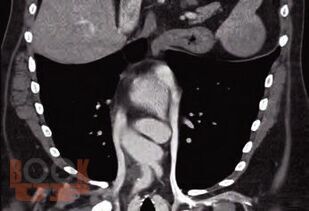

В книге представлены современные методы обеспечения сосудистого доступа у различных категорий пациентов с заболеваниями системы крови. Обсуждаются проблемы катетеризации вен как с учетом различных типов катетеров, так и особенностей течения заболеваний системы крови и проводимого лечения. Рассматриваются безопасные показатели для катетеризации при тромбоцитопении, врожденной и приобретенной коагулопатиях, тромбофилии, нейтропении, а также предпочтительные сосудистые доступы и типы катетеров для проведения противоопухолевой химиотерапии, трансплантации гемопоэтических стволовых клеток, заместительной терапии факторами свертывания крови, заместительной почечной терапии. Большое внимание уделяется осложнениям катетеризации, их профилактике и лечению. Книга содержит иллюстрации, которые демонстрируют различные аспекты рассматриваемых проблем. Представлен алгоритм по выбору типа катетера и сосудистого доступа у пациентов с заболеваниями системы крови. Рекомендуется гематологам, онкологам, анестезиологам-реаниматологам и медицинским работникам других специальностей, сталкивающимся в своей работе с обеспечением сосудистого доступа.